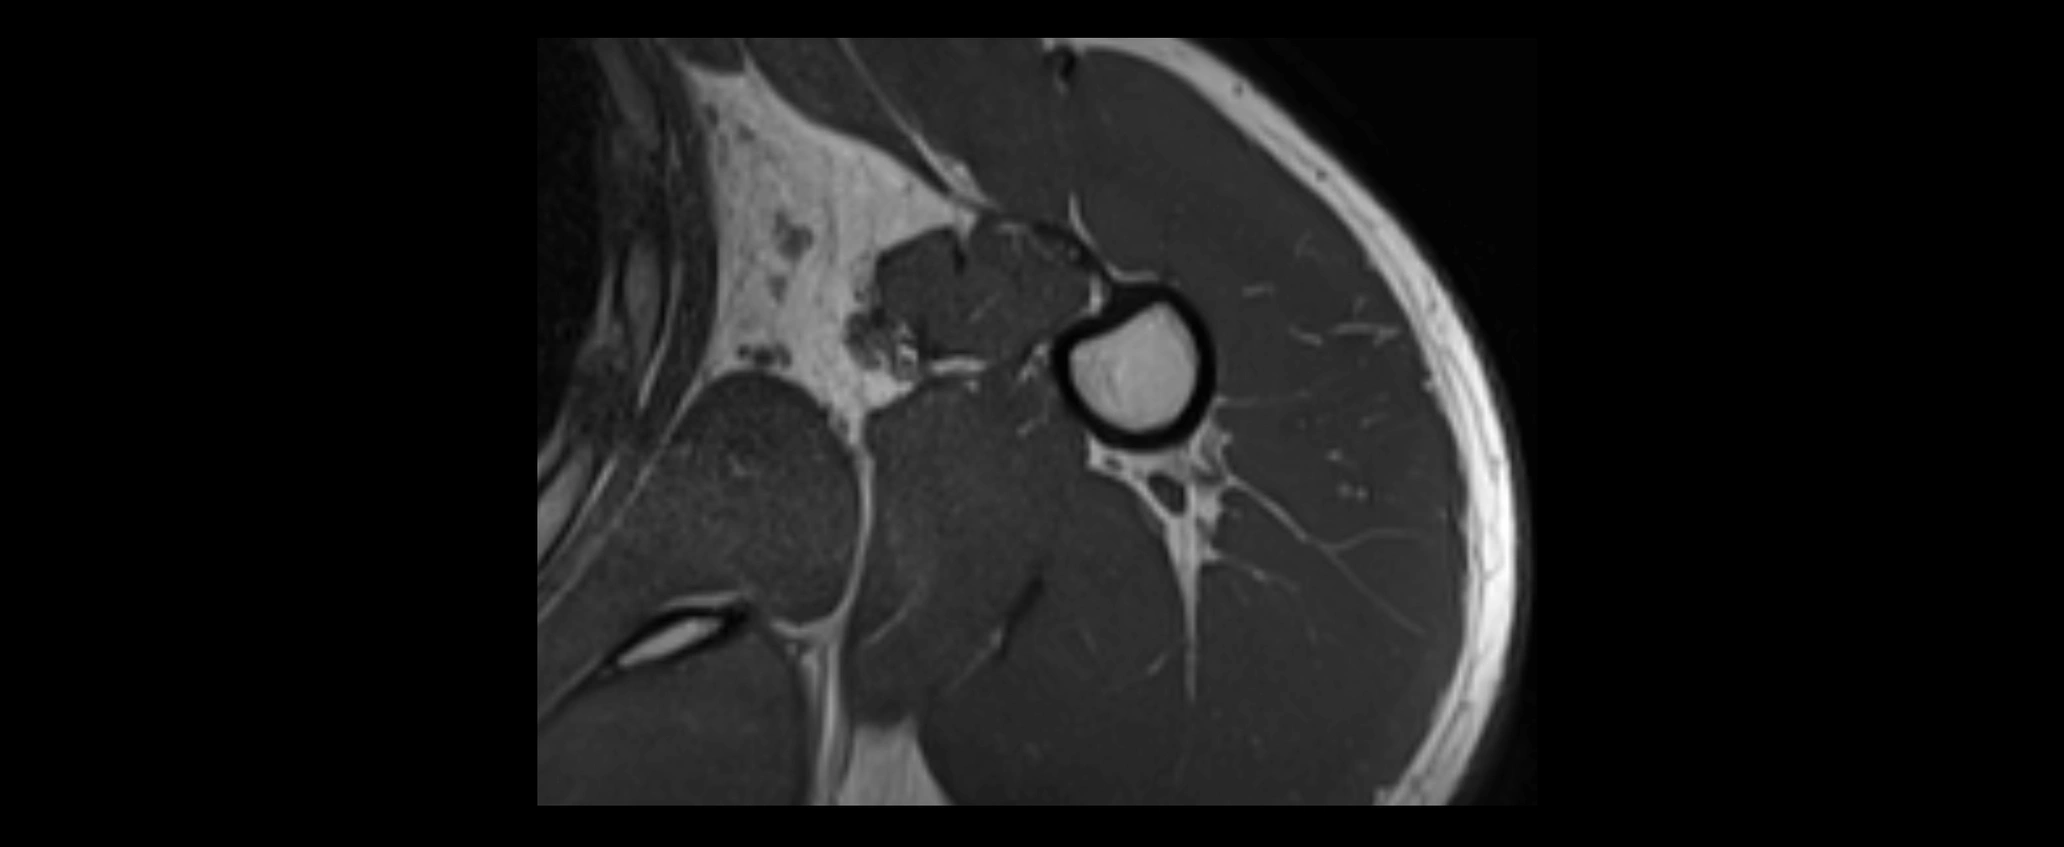

CT image

image